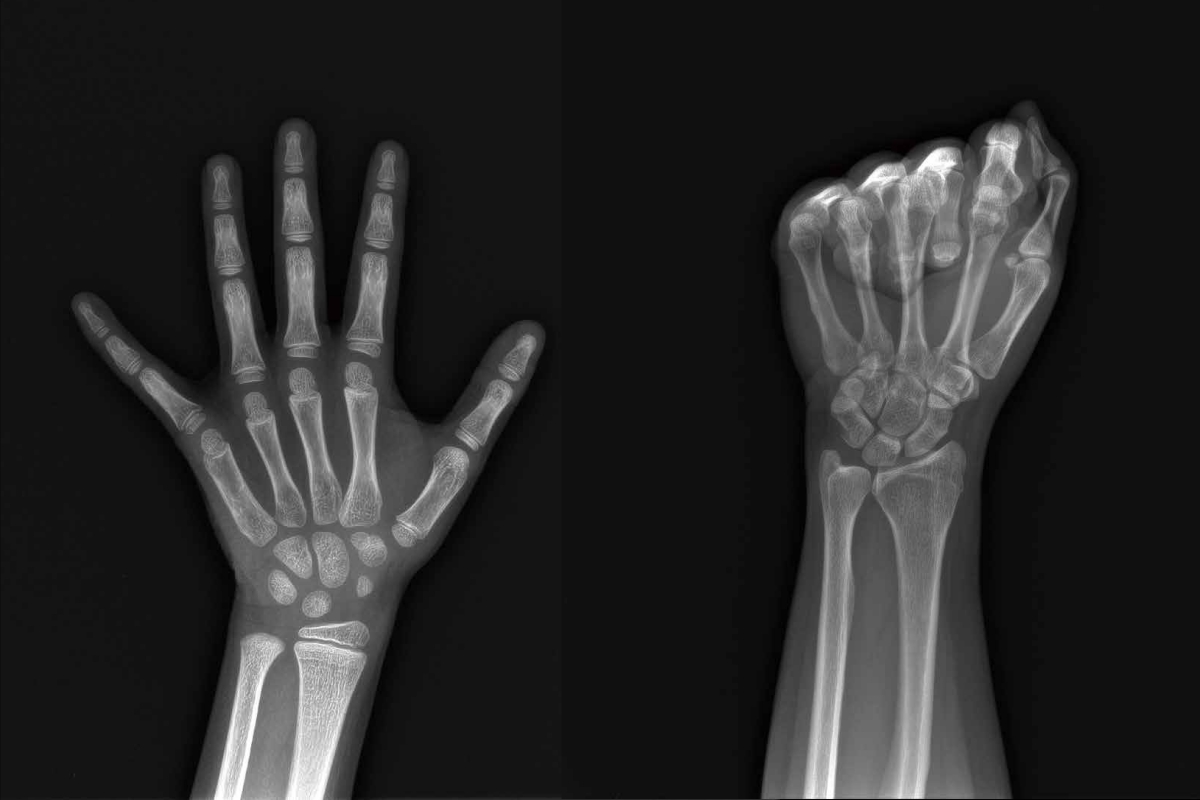

骨龄与骨密度有什么区别?解析两者的定义、检测与应用

在骨骼健康管理中,“骨龄”与“骨密度”常被并列提及,但二者本质截然不同:前者是生物年龄的“时间刻度”,后者是骨骼质量的“密度标尺”。本文将从医学原理、检测技术、临床意义三个维度,揭开这对“双生密码”的神秘面纱。

安智康生物自主研发的儿童手部X射线图像骨龄AI辅助评估软件,于2025年3月成功获批国家药品监督管理局三类医疗器械证(注册证编号:国械注准20253210620)。这也标志着,安智康生物成为国内同时具备骨龄检测硬件和骨龄AI软件三类医疗器械证的厂家!